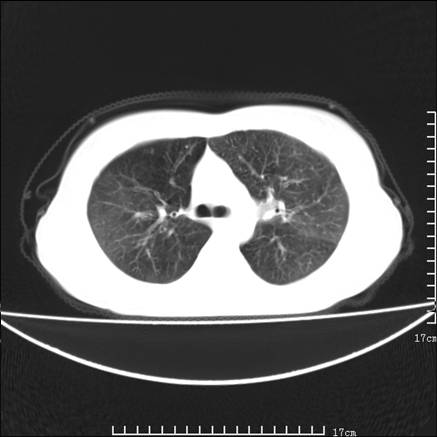

女,46岁,患胃溃疡多年,溃疡大小约1.0cm左右,后于5年前手术,病理为胃癌。主诉:半月前感冒后胸闷,气短,有咳嗽,无明显咳痰,无发热。偶有腰背部不适。

以下为高分辨扫描图像

双肺小叶间增厚,双肺散布粟米影和磨玻璃状影,以双肺上叶为重。结合病史考虑转移(癌性淋巴细管炎)可能性大。

结合病史:认为是典型肺部癌性淋巴管炎、淋巴结转移。请看图解。

正如caihe主任所言,影像表现结合临床病史应该支持肺癌性淋巴管炎;上肺大片边缘不清的渗出病变,多系感染所致,临床有感冒病史并咳嗽表现。肺癌性淋巴管炎临床一般无咳嗽、咳痰症状。

肺癌性淋巴管炎征象分为主要征象及合并征象,主要征象包括:

1、近肺门支气管血管周围间质结节状增厚;

2、小叶间隔结节状增厚;

3、小叶中央间质结节状增厚;

4、胸膜下间质结节状增厚。

合并征象为:纵隔淋巴结增大,胸腔积液,肺多发随机分布的小结节等。